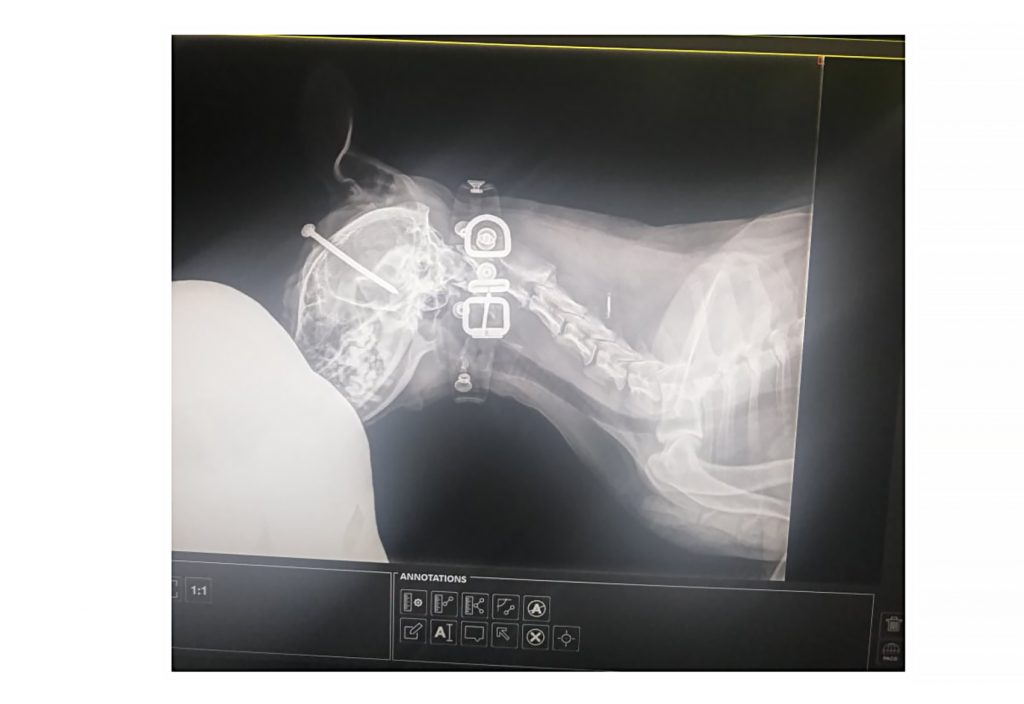

Ova firma jedina u Srbiji proizvodi rendgen aparate za humanu medicinu, a ne mogu da učestvuju na tenderima.

Inače, u DZ Vladičin Han, nabavka digitalnog radiografskog aparata pokrenuta je još 1. februara ove godine, a odluka o ponuđaču objavljena je 8. jula. Vrednost ugovora je 14.950.800 dinara, a dodeljan je prvo firmi “Visaris”, pa je tender vraćen, da bi ugovor dodelili kompaniji Beolaser, koja se bavi uvozom, distribucijom medicinske opreme stranih proizvođača.

Ova firma navodi diskriminatorne tehničke uslove koji favorizuju samo uređaje određenih stranih proizvođača, što se jasno vidi iz tenderske dokumentacije:

“U Apatinu se zahteva laserski štampač koji mora podržavati tačno pet formata filma, uključujući neuobičajeni i nepotreban format 35×35 cm, koji koristi isključivo uređaj američkog proizvođača Carestream, model DryView 5950, čiji je jedini zastupnik u Srbiji firma Medicom d.o.o. iz Šapca. Ovim se veštački postavljaju uslovi koje ne ispunjava nijedan drugi ponuđač osim navedenog.

U Pančevu, tehničke specifikacije detektora (npr. težina, broj LED dioda, nosivost) i laserskog štampača odgovaraju isključivo uređajima japanskog proizvođača Fujifilm, čiji je zvanični zastupnik firma Alpha Imaging d.o.o. iz Beograda. Time se eliminiše konkurencija i favorizuje konkretan ponuđač.

U Vladičinom Hanu ponuda “Visarisa” za aparat ”Vision V”, proizvođača Visaris d.o.o. odbijena je bez adekvatne provere i obrazloženja, iako je Republička komisija za zaštitu prava u postupcima javnih nabavki, naložila dodatnu proveru tehničkih karakteristika aparata koju naručilac nije izvršio”.